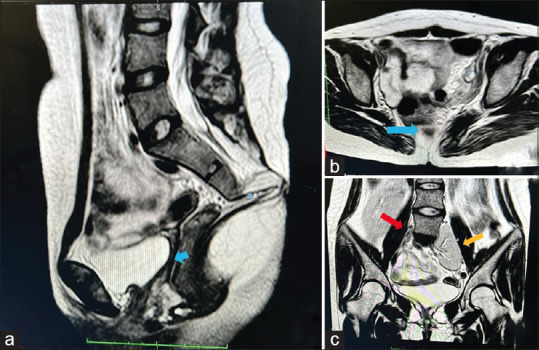

视网膜血管闭塞在年轻人中很少见,任何闭塞都需要进行广泛的临床评估以确定病因。心脏畸形是栓塞的来源之一。我们介绍了一例患有心房间隔缺损(ASD)的 II 型 Mayer-Rokitansky-Küster-Hauser 综合征患者,该病导致一名年轻女性出现单侧视网膜分支动脉闭塞(BRAO)。一名 21 岁女性患者突然出现无痛性视力模糊和右眼上视野缺损。眼底检查确诊为 BRAO。眼部和全身评估显示她患有原发性闭经、ASD、异位肾脏和盆腔囊肿。必须对年轻患者的任何血管闭塞进行彻底评估,包括详细的系统病史。

Retinal vascular occlusions are rare in young people, and any occlusion warrants an extensive clinical evaluation to establish the etiology. Cardiac malformations are a source of embolism. We present a case of atrial septal defect (ASD) in a patient with type II Mayer-Rokitansky-Küster-Hauser syndrome, leading to unilateral branch retinal arterial occlusion (BRAO) in a young woman. A 21-year-old woman presented with sudden, painless, blurring of vision, and a superior visual field defect in her right eye. A fundus examination confirmed the BRAO diagnosis. Ocular and systemic evaluation revealed primary amenorrhea, ASD, ectopic kidneys, and pelvic cyst. Any vascular occlusion in a young patient must be thoroughly evaluated, including a detailed systemic history.